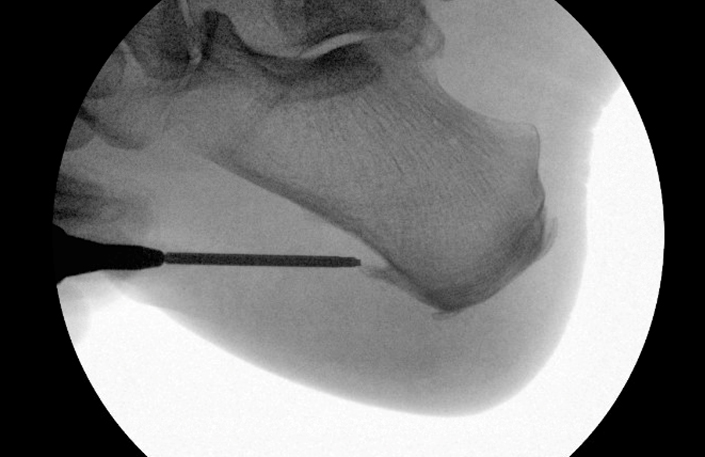

TOTAL ANKLE REPLACEMENT :: ORIF CALCANEUS :: ORIF ANKLE FRACTURE DISLOCATION :: COMPLEX BUNION AND LESSER TOE CORRECTION :: TALUS FRACTURE -1 :: TALUS FRACTURE -2 :: LISFRANC REPAIR :: COMPLEX TRIPLE ARTHRODESIS 1 :: COMPLEX TRIPLE ARTHRODESIS 2 :: MINIMALLY INVASIVE BUNION REPAIR 1 :: MINIMALLY INVASIVE BUNION REPAIR 2 :: ARTHROSCOPIC CARTILAGE REPAIR :: TENEX SPUR DEBRIDEMENT :: Haglunds Debridement and Achilles Repair